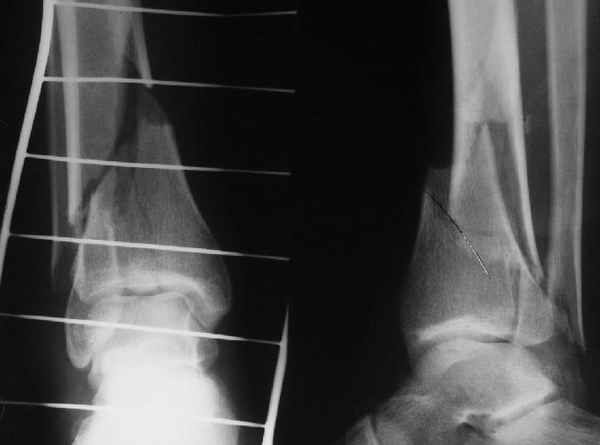

Традиционная техники АО, открытая, с точной репозицией суставной поверхности и жесткой фиксацией, из-за серёзных осложнений, которые

заканчивались ампутацией, уходит в прошлое.

Техника сегодня более щадящая, временные несложные аппараты наружной фиксации: Spanning 2 pin ExFix, Traveling traction для лигаментотаксиса, иначе сокращенные мягкие ткани невозможно восстановить позже.

За последнее 10-12 лет после стабилизации малоберцовой кости, стали применять более усовершенный, сложный, хорошо вам известный метод

Илизарова (кстати наряду с тибиал плато, пилон является одним из показанием по применению аппарата Илизарова при травмах) или Hybrid

Fixator, из минимальных доступов комбинированный метод для восстановления суставной поверхности-фиксация каннулированными

шурупами, создания жесткой системы фиксации до сращения перелома, защита от вальгусной деформации и на место образовавщегося метафизарного дефекта- костная пластика ауто костью или его

синтетические заменители, это сегодняшная тактика лечения.